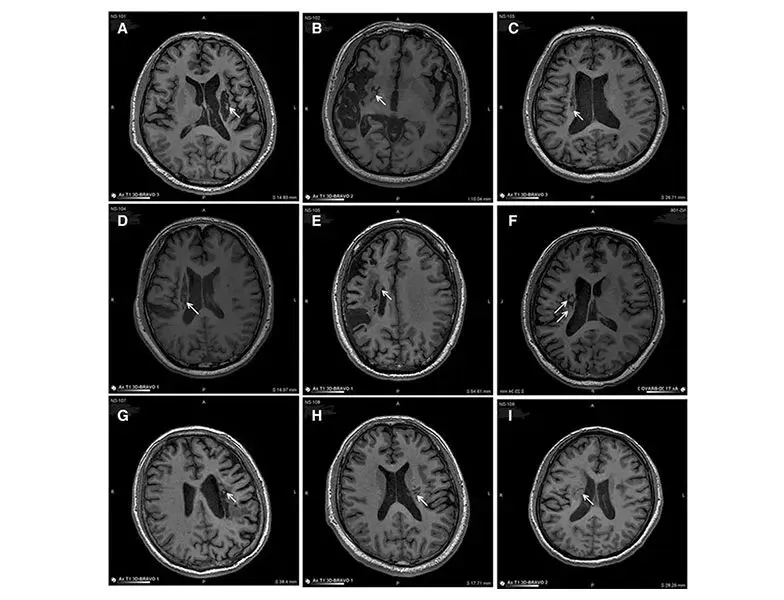

△ 9例患者的影像学显示病变区域的组织都发生了明显变化

从影像学上可以明显的看到,移植到脑内梗塞病灶的干细胞,通过分化为神经系统的各类细胞、分泌营养因子,促进神经和血管再生,修复受损的血-脑脊液屏障,减轻炎性反应等促进脑梗死动物的神经功能恢复,让9例临床患者偏瘫的症状得到了明显改善。